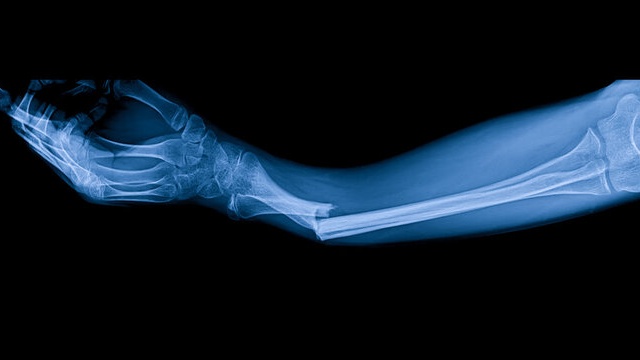

Gãy xương cẳng tay là tình trạng phần xương từ khuỷu tay đến cổ tay bị gãy. Đây là một trong những chấn thương phổ biến nhất, chiếm tới gần 5% các bệnh gãy xương. Tùy thuộc vào nguyên nhân, lực tác động và vị trí, xương cẳng tay có thể gãy chéo, gãy ngang, gãy vụn. Những dấu hiệu phổ biến để nhận biết là:

Với thắc mắc “Gãy xương cẳng tay bao lâu thì lành?”, nhiều bác sĩ cho biết thời gian điều trị sẽ phụ thuộc vào mức độ chấn thương và sức khỏe hệ xương khớp của người bệnh.

Trung bình, một người bình thường sẽ cần bó bột để cố định phần bị gãy từ 2 - 3 tháng. Thời gian để bình phục hoàn toàn là từ 5 - 6 tháng. Tuy nhiên, đối với những người già, người thiếu canxi, quá trình bình phục sẽ diễn ra lâu hơn do xương khớp đã bị giòn xốp, thoái hóa.